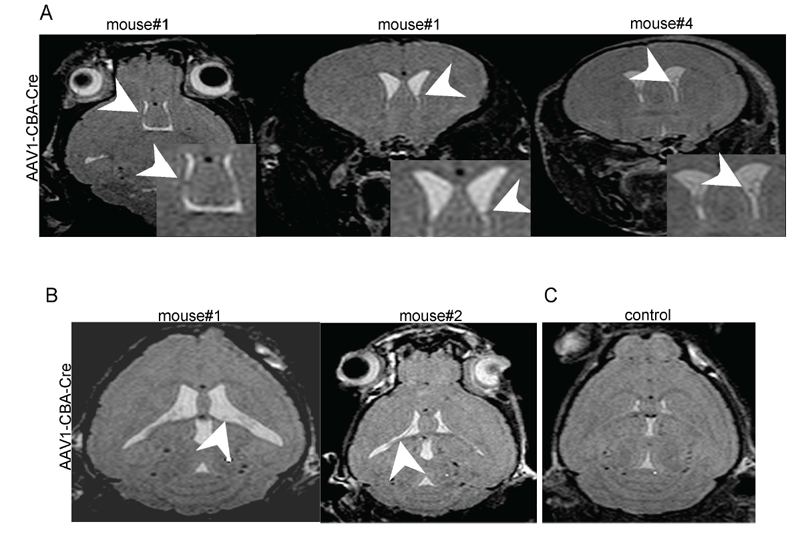

Caption Representative magnetic resonance images (MRI) of AAV1-CBA-Cre and AAV1-CBA-GFP injected Tsc1tm1Djk/Tsc1tm1Djk Gt(ROSA)26Sortm1Sho/Gt(ROSA)26Sor+ mouse brains. AAV1-CBA-Cre injected mouse brains showed abnormalities associated with the ventricular regions. (A) Multiple apparent subependymal nodules (arrowheads) were seen in the ventricles in the brains of two AAV1-CBA-Cre injected mice. First two images are from the same mouse. (B) Ventricles also appeared to have thickening of the ependymal lining (arrowheads; two left panels). (C) None of these abnormalities were observed in the control vector (AAV1-CBA-GFP)-injected brains